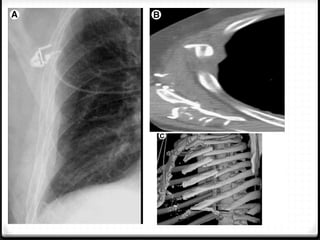

0 X-ray and CT

 x-ray : limited sensitivity, helpful >>  Oblique >> AP/PA

 CT scan : most sensitivity

Pneumothoraks

0 Udara pada rongga pleura

0 15%–40% ditemukan pada trauma thoraks

0 Ruptur alveoli karena ada tekanan meninggi secara tiba-tiba

pada intrathorakal akibat trauma dengan atau tanpa fraktur

costae

0 Radigrafi polos >>

0 ± 10% tidak dapat dievaluasi dengan radiografi polos  CT scan